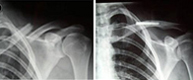

Fracturas de clavícula

Fractura clavículaFractura clavículaLas fracturas de clavícula representan del 10 al 16% de todas las fracturas de nuestro esqueleto y son las fracturas más frecuentes de la infancia. Afectan fundamentalmente a su tercio medio (75%) y no suelen producirse por impacto directo sobre ella, sino, por una caída sobre el hombro, el cual transmitela fuerza deformante hacia la clavícula produciendo su fractura.